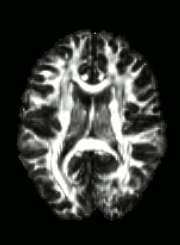

Quality Assessment

DWI

FA

SSE